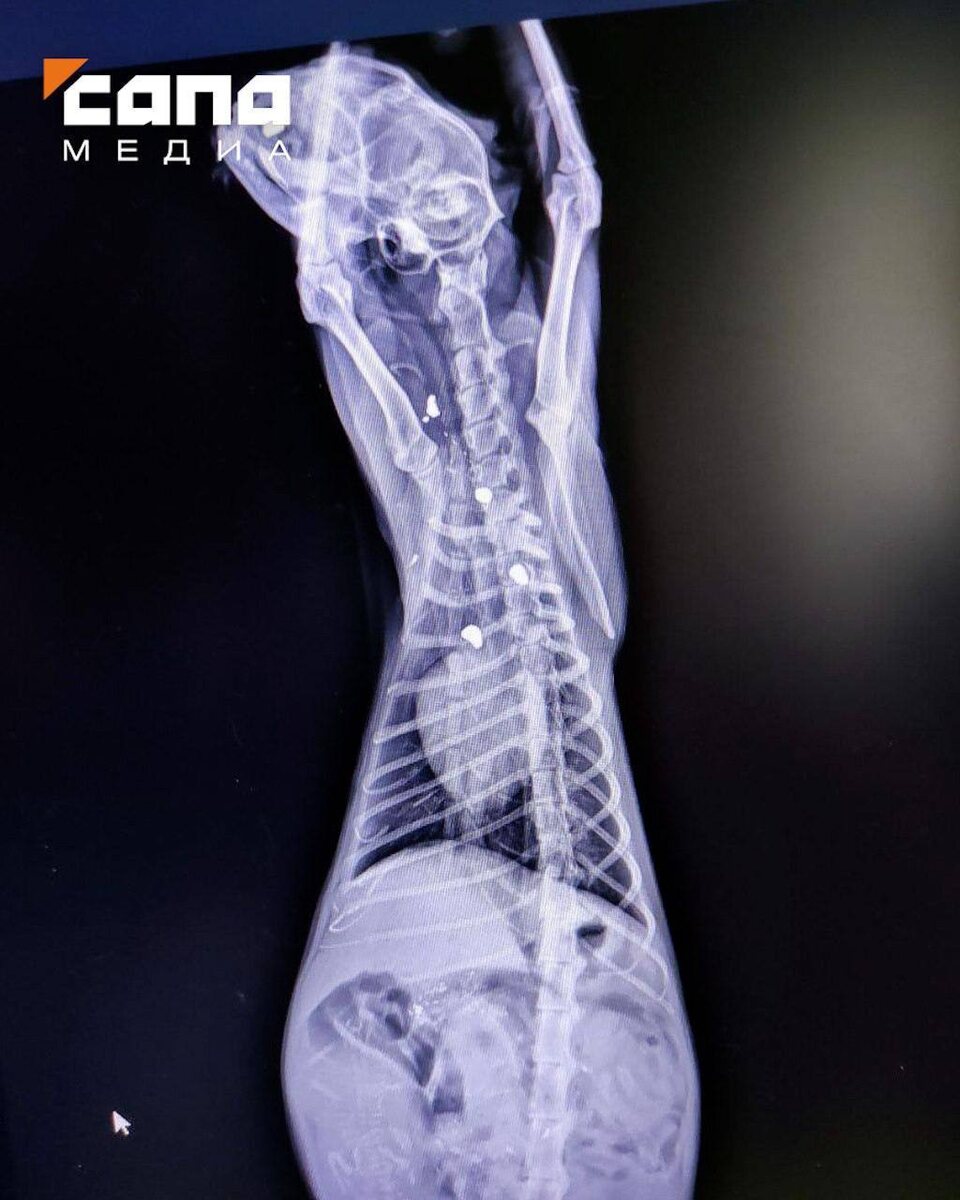

Последнюю кошку волонтерам принесли из аэропорта «Владикавказ». У нее нашли одну пулю в носу, три — в теле.

На рентгеновском снимке раненой кошки видны застрявшие пули